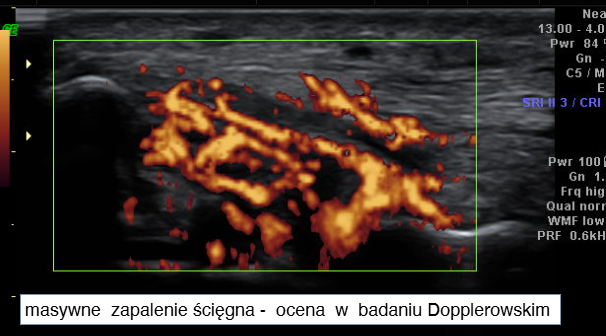

3. Zapalenie ścięgien

Badanie pokazuje:

- pogrubienie ścięgien,

- zwiększoną echogeniczność,

- obecność płynu,

- zmiany przewlekłe.

Dotyczy często:

- ścięgien strzałkowych,

- piszczelowego tylnego.

4. Wysięk i stan zapalny stawu

USG pozwala wykryć:

- płyn w stawie,

- zapalenie błony maziowej,

- aktywność zapalną (Doppler).